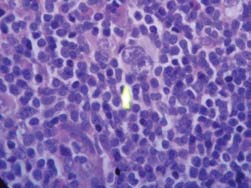

Histológicamente se observa un ganglio linfático con arquitectura totalmente alterada por proliferación interfolicular y paracortical, que borra los folículos y los cordones medulares. Esta proliferación está formada por eosinófilos, linfocitos pequeños, células plasmáticas y macrófagos, además de células grandes mononucleadas, binucleadas y polinucleadas. En estas últimas, los núcleos son grandes con cromatina laxa casi vesiculares con un nucléolo prominente acidófilo. Las células binucleadas presentan núcleos frente a frente, mostrando una imagen en espejo. No se observa necrosis y la cápsula es delgada pero infiltrada por linfocitos.

Fig 2.- Célula binucleada con nucléolos acidófi los prominentes y eosinófi los en la parte superior.

La clasificación también cambió en los últimos años y hoy se consideran dos variedades: el linfoma de Hodgkin predominantemente linfocítico nodular y el linfoma de Hodgkin clásico, este último continúa con los 4 subtipos: predominio linfocítico, esclerosis nodular, celularidad mixta y depleción linfocitaria6,7. El linfoma de Hodgkin con celularidad mixta se caracteriza por presentar una cápsula delgada, sin fibrosis ni en los septos internos, proliferación difusa de eosinófilos, linfocitos, células plasmáticas, polimorfonucleares e histiocitos, con células neoplásicas mononucleares o células de Hodgkin, células binucleadas típicas o de Reed-Sternberg, presente en la Fig 2, y escasas células lacunares con abundante citoplasma claro. Para el diagnóstico, es imprescindible encontrar la célula de Reed-Sternberg.